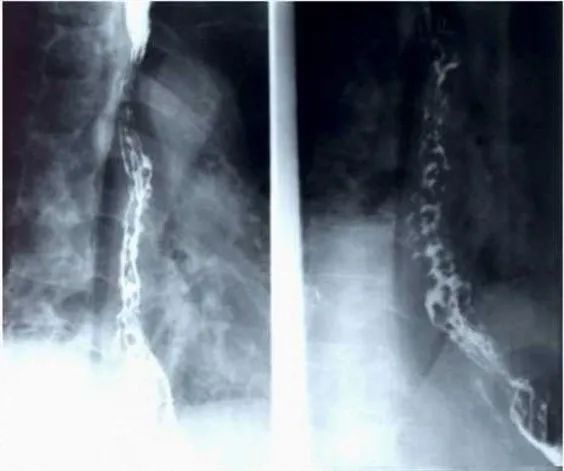

上點難度,你們都不一定猜的出來的。

這是啥?一般人可能還真看不出來,這是食道鋇餐檢查,這串珠樣的改變提示食管靜脈曲張。

這麼模糊的圖像竟然答對了檢查方法,而且也説出了關鍵詞“串珠樣”改變,可惜答案錯了,竟然答成了瀰漫性食管痙攣。這是我第一次聽到這個病。

不愧是胡編亂造第一名的ChatGPT。